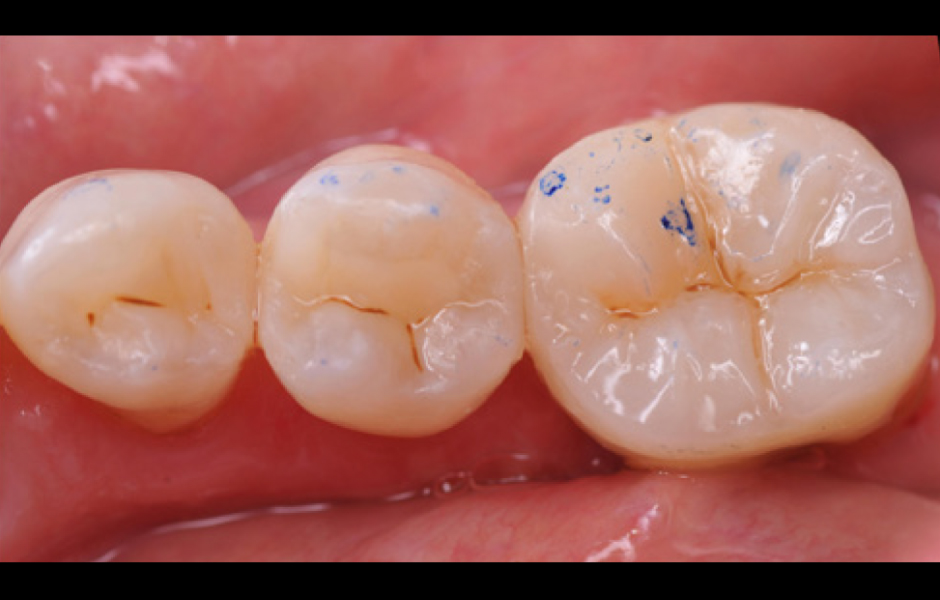

Obr. 10: Odstranění kofferdamu. Po odstranění kofferdamu byly výplně a onlay finálně opracovány a vyleštěny.

Obr. 11: Kontrola okluze. Nakonec byly zkontrolovány okluzní kontakty a dle potřeby upraveny.